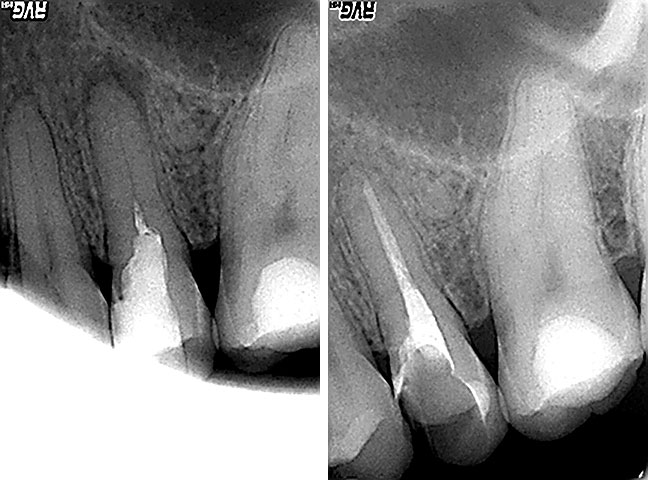

RTG dijagnostika

Endodoncija